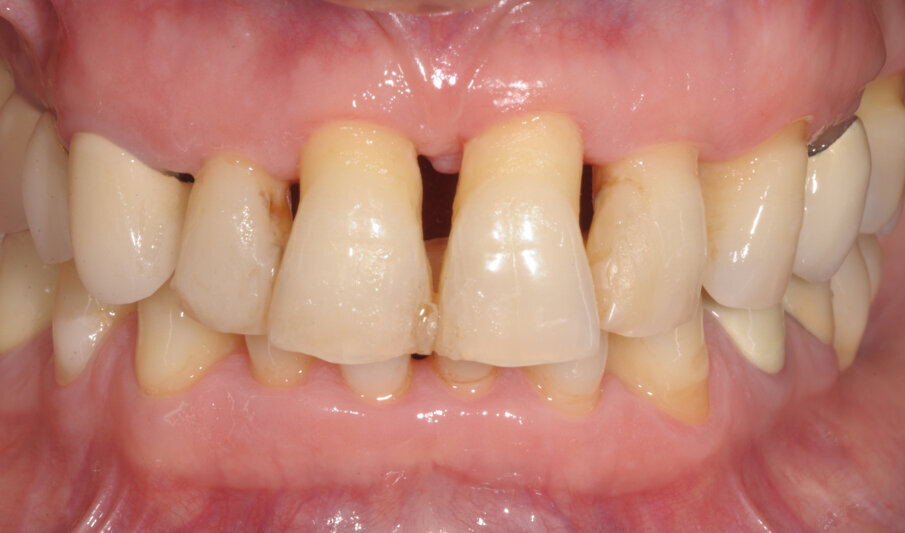

Paziente di sesso femminile, 56 anni, affetta da malattia parodontale cronica con annessa perimplantite in zona 36. La paziente è allergica alla clorexidina ed in oltre riferisce una non tolleranza ideologica per le cure chimico-farmacologiche in genere.

A termine del trattamento descritto in precedenza da un punto di vista clinico abbiamo ottenuto un ripristino dei parametri di salute dell’impianto ovvero la scomparsa del sanguinamento dell’edema e della purulenza, in oltre si è verificata una riepitelizzazione dei tessuti molli limitrofi l’impianto. Da un punto di vista radiografico abbiamo ottenuto la neoformazione di osso attorno alle spire dell’impianto (con relativo aumento della stabilità) che a inizio terapia era da considerarsi potenzialmente come perso. La radiografia a 60 gg prima ed a 1 anno mostrano quanto prima descritto, ovvero un ripopolamento di componenti cellulari ossei sull’impianto con un recupero di 3 spire implantari (Figg. 7-9).